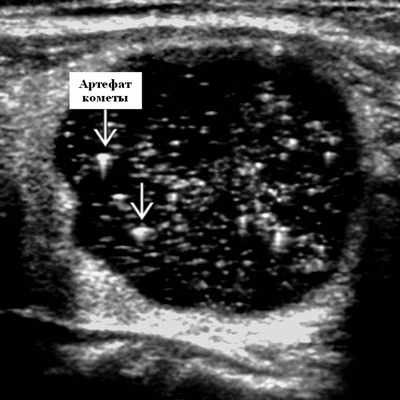

Серошкальное УЗИ. Множественные узлы, двустороннее диффузное вовлечение обеих долей. Солидные узлы часто изоэхогенные, с небольшой долей гипоэхогенных (5%). Несмотря на то, что они не инкапсулированы, узлы резко очерчены и имеют ореол - хало, который состоит из сосудов и сжатой щитовидной железы. Гетерогенная эхоструктура с внутренним детритом, перегородками, солидными и кистозными участками. Сплошная часть внутри узлы часто представляет собой сгусток крови. Плотное затенение кальцификации (криволинейное, дисморфное, грубое) ± множественное. Узлы с артефактом из хвоста кометы очень напоминают коллоидный узел (имитирует микрокальцификацию). Кистозный компонент возникает из-за дегенерации, кровоизлияния или коллоида в узле. Фоновые паренхиматозные эхоструктуры щитовидной железы являются грубыми и неоднородными (тонкие яркие эхосигналы в нормальной железе).